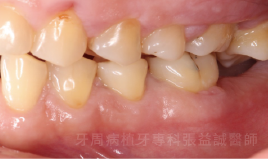

治療前 治療後

治療前

治療後